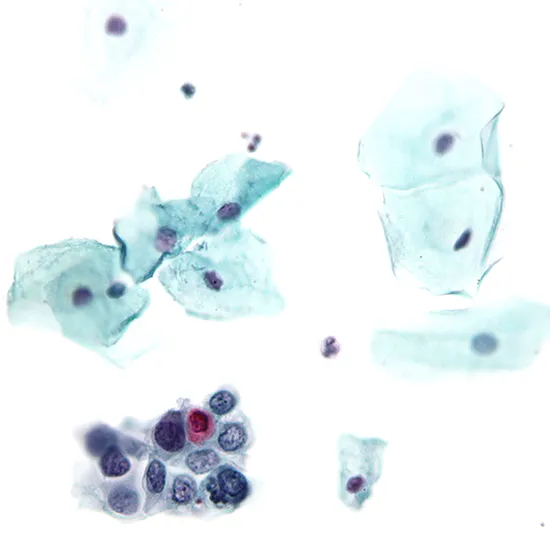

pap smear cytology test

A Pap smear, alternatively called a Pap test, is a test performed to detect malignant or precancerous cells on the cervix. Cervix refers to the lowest portion of the uterus that attaches to the vagina. A Pap smear is performed by swabbing or brushing cells from the cervix's surface during a pelvic check-up.

A Pap smear is primarily used as a cervical cancer screening test. Additionally, this test may detect additional health issues, including infections, inflammation, and different types of cancer.